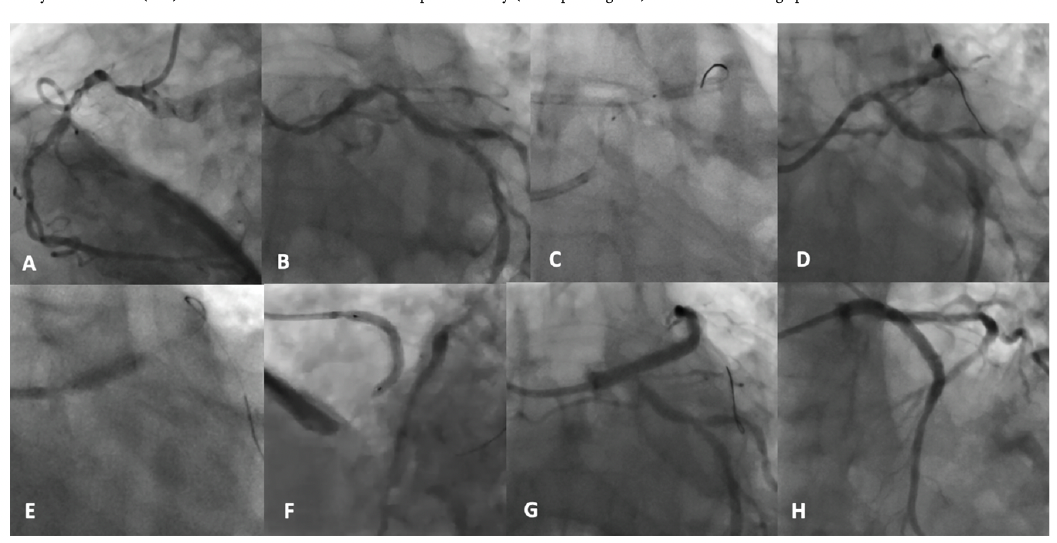

With a 6 French (F) Extra Backup (EBU) 3.5 guide (Medtronic) and a guide extension catheter (GEC), it was eventually possible to deliver a small 1.1 mm Across CTO balloon (Acrostak) through the nodular distal LM and ostial LAD calcium, and then undertake sequential pre-dilatation with incrementally larger balloons up to 3.0 mm, with restoration of some flow and ST segment improvement.

Intravascular ultrasound (IVUS) imaging (Figure 1B) showed all varieties of calcium throughout the LAD and LM. A 4.0 intravascular lithotripsy (IVL) balloon (Shockwave Medical) was used to modify calcium with the support of intracoronary phenylephrine to elevate baseline blood pressure prior to each 10-pulse delivery (20-30 pulses given) across the LM. This enabled modification without grossly compromising hemodynamics. A 3.5 mm x 48 mm Xience stent (Abbott Vascular) was deployed and optimized, with a final IVUS run showing good expansion and apposition. There was some eccentricity to stent expansion as expected with nodular calcium, but with a good area within the LM of more than 12.5 mm2. There was moderate disease in the circumflex that did worsen slightly after jailing with the stent. I briefly tried to cross, but with angulation and calcium, the support was not adequate.

We returned the patient to the coronary care unit with a plan to potentially bring him back for a staged procedure with 7F equipment to complete the circumflex and also to treat the right coronary artery. However, at 48 hours, he was walking down to the coffee shop, completely chest pain-free, and he pragmatically declined further intervention. After a PCI multidisciplinary heart team meeting and discussion with him and his family, we agreed that at 85 years and in accordance with his wishes, this was a reasonable decision. He has been medically managed since and is now over 2 years post PCI with an unlimited exercise tolerance. He has not returned with angina or a recurrent cardiac event.